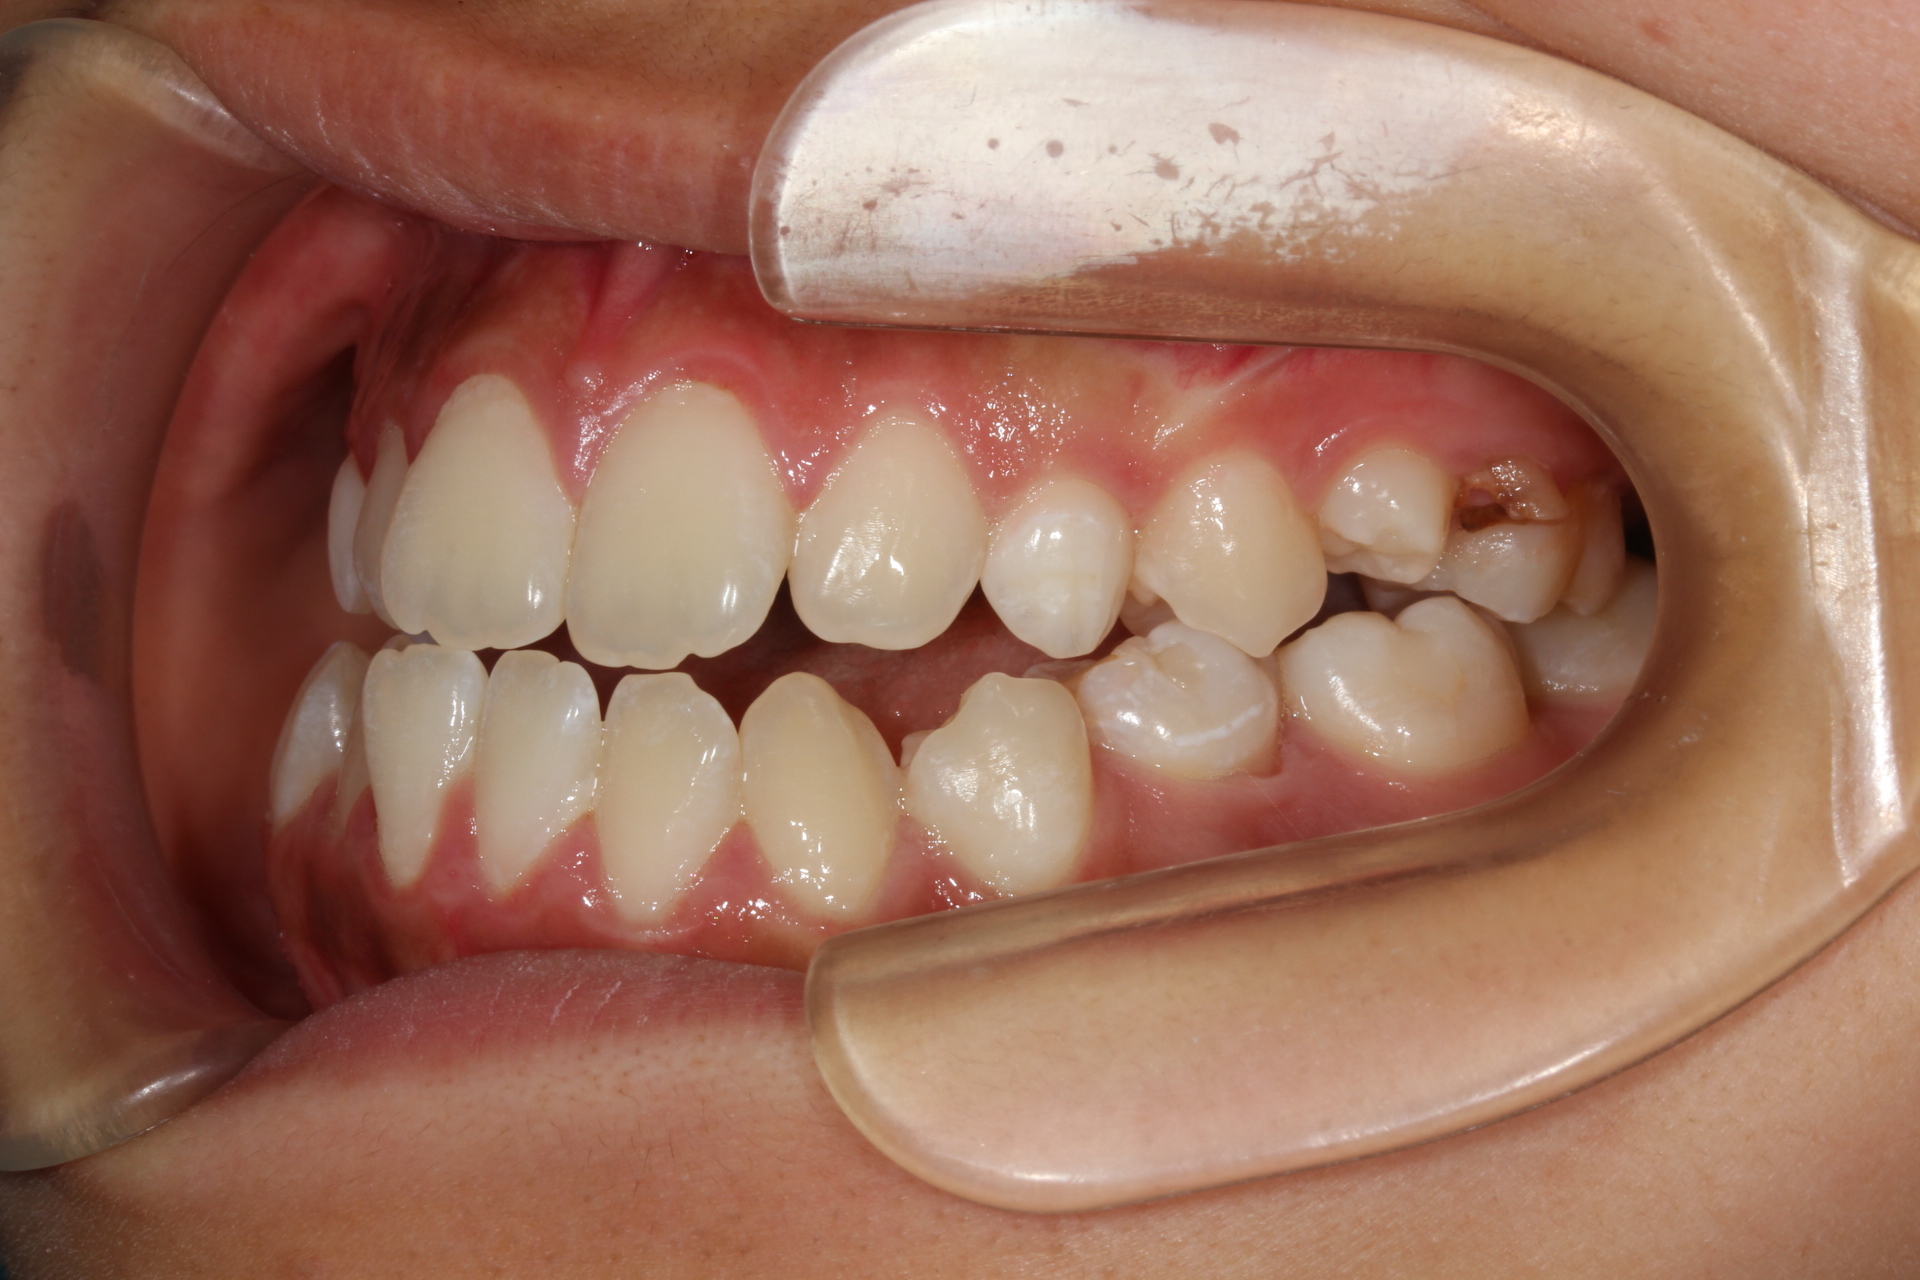

10代女性。 主訴「下アゴが出ている」。

骨格性下顎前突で本来なら外科矯正のケースであるが本人の強い希望により矯正治療のみで咬合改善を行う。

まずは前歯部の被蓋関係改善の為に、Carriere MotionとⅢ級エラスティックを使用し下顎の後退を行う。その後マルチブラケットにて永久歯咬合関係の改善を行った。

本来なら外科矯正を行うケースを矯正治療のみで行っていることから、顔貌の改善はできていない。また理想的なⅠ級咬合は獲得できていない。今後の成長発育によっては後戻りの可能性あり。